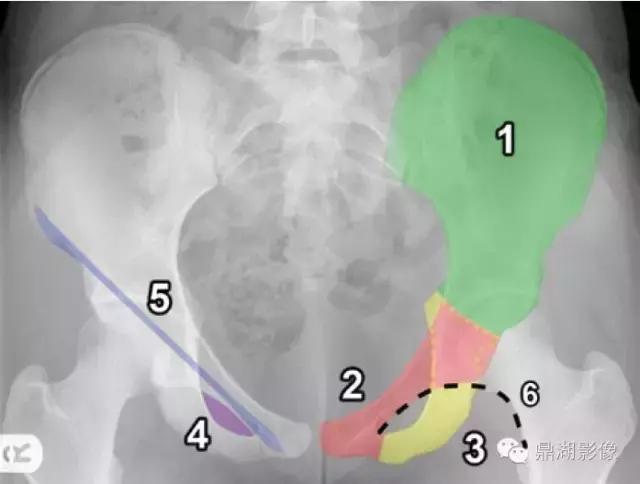

1.髂骨(绿色) 2.耻骨(红色) 3.坐骨(黄色) 4.闭孔(紫色) 5.右腹股沟韧带的位置(蓝色)。腹股沟韧带运行髂前上棘和耻骨之间结节 6.Shenton’s线(黑色轮廓)